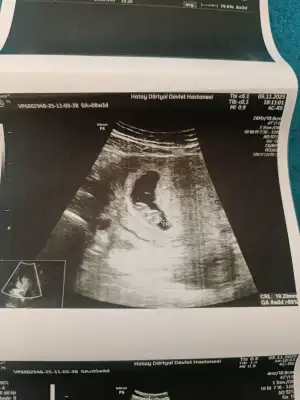

Merhaba arkadaşlar ben de haziranda doğum yapacağım ikili test yaptırdık bir problem çıkmadı fetal dna da yaptıracağız biz. Şu an 13+3 haftalık hamileyim ☺️ cinsiyet tahmini yapabilir misiniz ? Doktorumuz bir tahminde bulundu ama net bir şey diyemem dedi yüzdelik bile belirtmedi 10 ve 13. Haftalık fotoğraflarını bırakıyorum